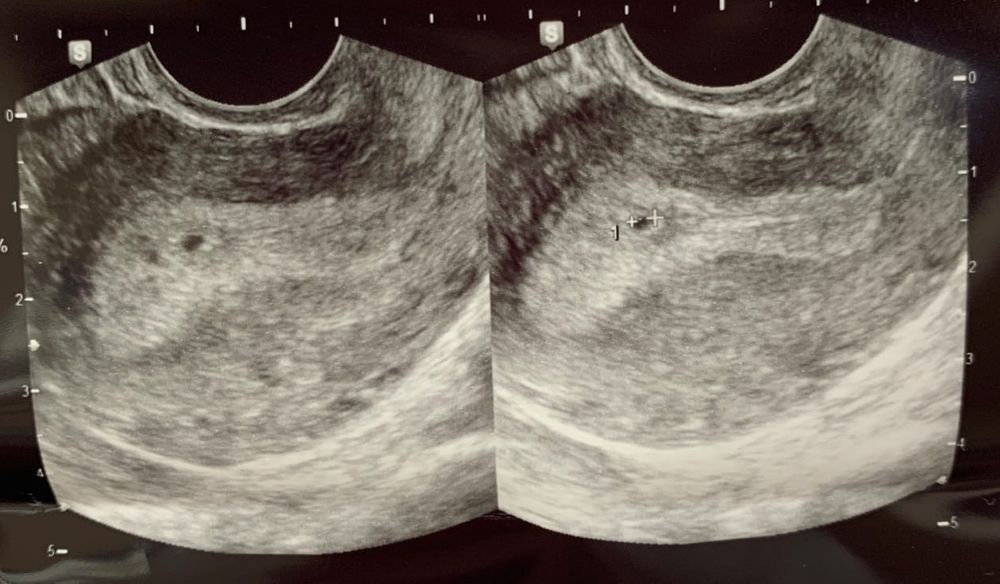

Сходила на первое УЗИ, срок от ДПМ 5 недель. Врач увидела ПЯ в матке 2,4 мм, но сказала, что еще не совсем опустилось куда нужно. Назначила пить дюфастон по 1т*2рд. О нем везде противоречивые отзывы, во многих странах он вообще запрещен. Я врачу своему доверяю, конечно. Но хотелось бы услышать вашего мнения. У кого такое было?)

Karmilla, написано ПЯ в дне матки. Снимок УЗИ вот. Сказала, что оно посредине. Пока что половой покой и дюфастон, пока на 2 недели.